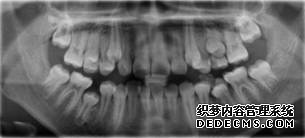

全景机正位片

临床诊断:通过3D数字化全景机的拍片检查,患者上下牙排列拥挤,前牙受挤压向内歪斜,咬合关系异常,唇形尚可,颞下颌关节检查未见异常,无蛀牙、牙周疾病症状。经过和患者商量,选定自锁托槽矫正方案,调整牙间隙,恢复牙齿的正常排列,实现正常的咬合关系。